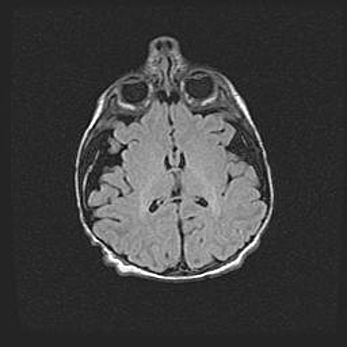

Неполная лизэнцефалия (пахигирия). Открытая гидроцефалия.

Возраст: 17 дней

Вес: 3110 г

Пол: мужской

Окружность головы: 33,5 см

Срок гестации: 35-36 недель

Лизэнцефалия—недоразвитие корковой пластинки и мозговых извилин в результате нарушения миграции нейронов коры. Поверхность мозговых полушарий гладкая. Микроскопически выявляется отсутствие нормальных слоев коры и скопление групп нейронов в подкорковом белом веществе.

Пахигирия—уменьшение числа вторичных извилин. В пораженном полушарии нервные клетки образуют толстый недифференцированный слой с неправильно расположенными нервными волокнами и группами гетеротопных клеток. Нервные клетки незрелые. Белое вещество истончено. При этом нередко аномально развит корково-спинномозговой путь.